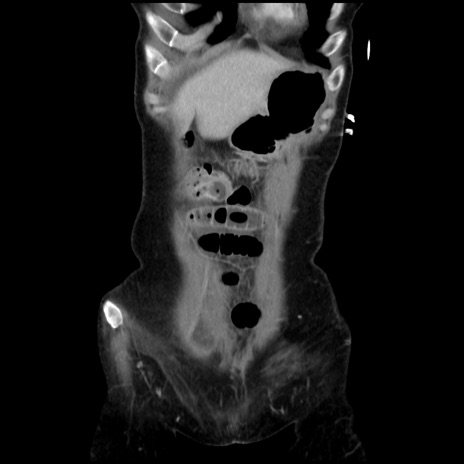

症例32(冠状断像)

【症例】40歳代 女性

【主訴】上腹部痛、嘔気・嘔吐

【現病歴】約9時間前頃から急に上腹部痛、嘔気、嘔吐が出現。改善しないため救急要請。

【既往歴】子宮頚癌(広汎子宮全摘術、放射線療法)、腸閉塞

【身体所見】腹部:平坦、軟、腸雑音亢進、上腹部を中心に腹部全体に圧痛あり。

【データ】WBC 8400、CRP 0.03